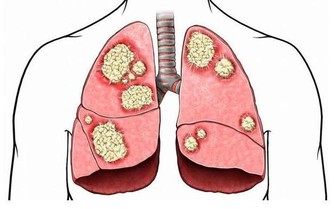

高密度脂蛋白被稱為「好膽固醇」,因為它負責將血管中的多餘膽固醇帶回肝臟代謝,防止膽固醇沉積在血管壁上形成斑塊。這有助於降低心血管疾病的風險,特別是動脈粥樣硬化、心臟病和中風。

HDL如同體內的「清道夫」,透過逆向膽固醇運輸機制,清除血液中的多餘膽固醇並將其排出體外。因此,HDL在維持血管健康方面發揮了積極的保護作用。